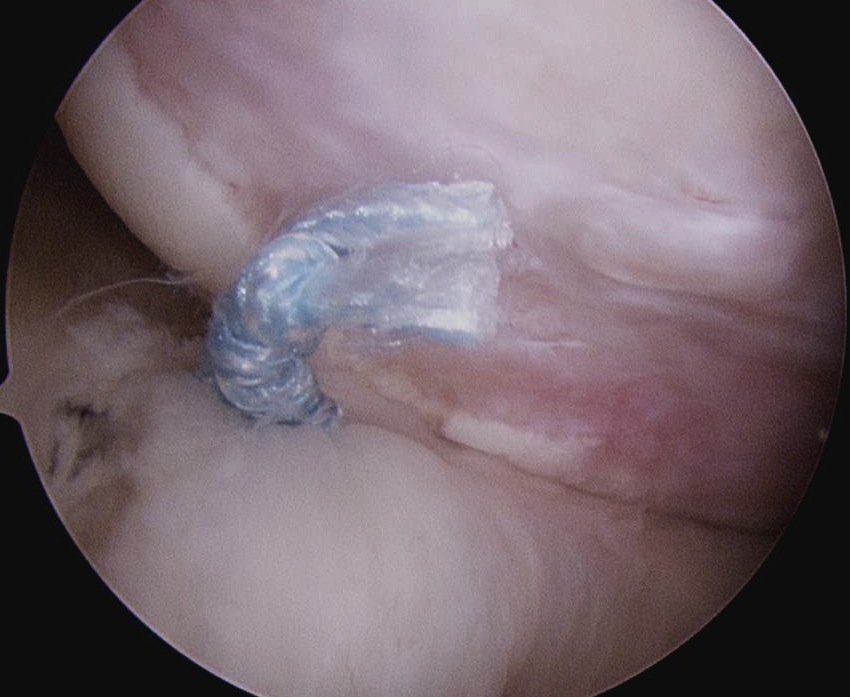

- insert anchors at medial aspect of defect

- suture passer / birds beak to take bite of capsule

- tie down into defect

Anchor insertion into Hill Sachs lesion